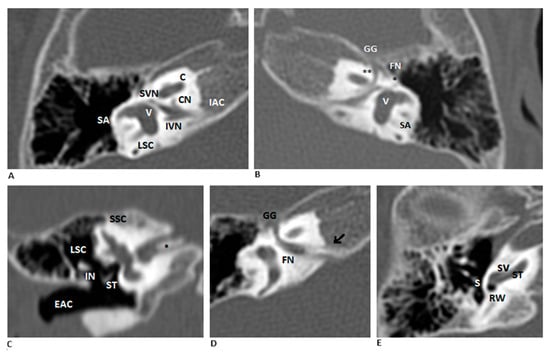

High-resolution CT and MRI revealed a duplicated appearance of the internal auditory canal (IAC) with normal cochlear and vestibular structures. The two canals were separated by a bony septum, delineating an anterosuperior facial nerve canal and a posteroinferior vestibulocochlear nerve canal (Figure 1).

Bilateral DIAC in CT scan. (A,B) Coronal HRCT images of the right and left ears show a bony septum dividing the IAC into an anterosuperior facial nerve canal and a posteroinferior vestibulocochlear nerve canal. Relevant structures include the facial nerve (FN, ** labyrinthine segment, * tympanic segment), cochlear nerve (CN), inferior vestibular nerve (IVN), and superior vestibular nerve (SVN). (C–E) Right ear details show the bony septum (* in figure C, arrow in figure D), a normal middle ear and external auditory canal (EAC), and a cochlea with normal morphology. Abbreviations: SA—subarcuate artery; V—vestibule; LSC—lateral semicircular canal; GG—geniculate ganglion; SSC—superior semicircular canal; ST—stapes; IN—incus; RW—round window; SV—scala vestibuli; ST—scala tympani.